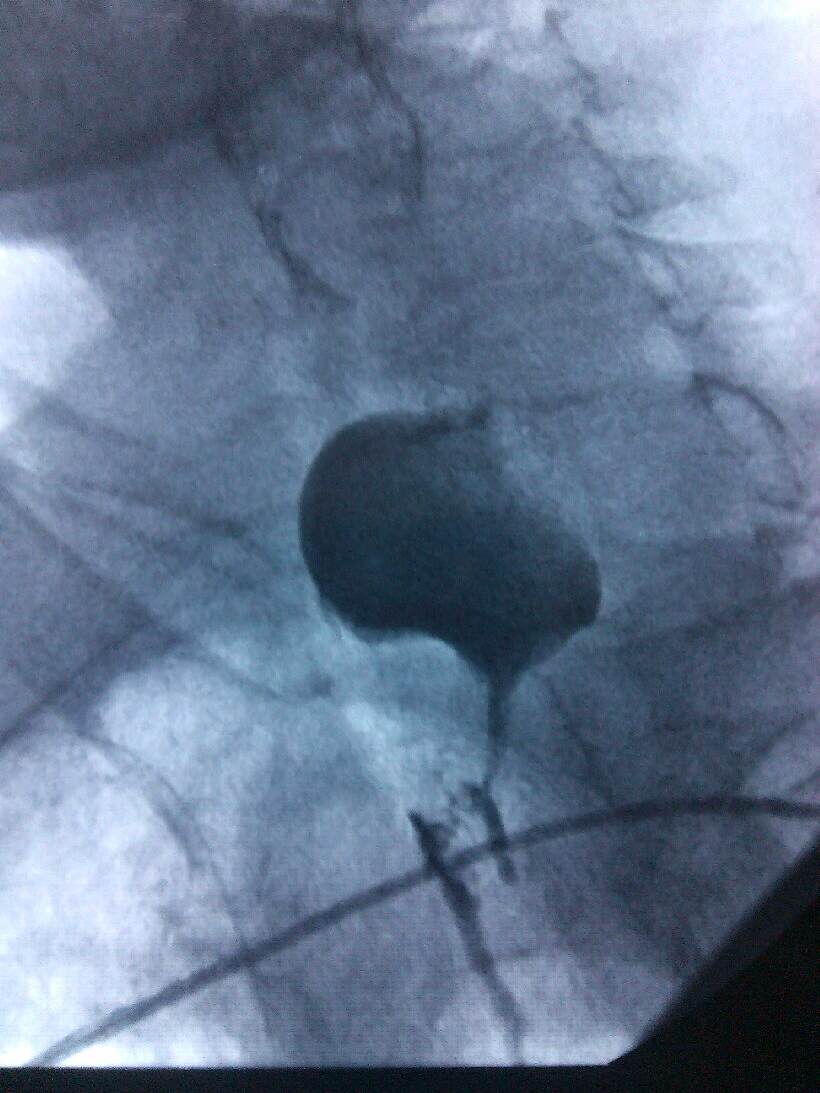

肿瘤科医生仔细检查,该患者肿瘤梗阻的位置高,咽喉及上段食管分泌物无法入胃,经常返流至气管,且分泌物特别多,造成患者非常痛苦,经常夜间被分泌物刺激,咳嗽难忍,无法入睡,造成患者生活质量极差。

根据病人的的身体条件,无法采用手术、放疗、化疗进行治疗。肿瘤科主任、副主任医师熊小平组织医生详细分析患者的病情,找到病因所在,制定周密的治疗方案,运用食管支架植入法将食管扩张,这样既解决了患者的“吃饭”问题,又解决了分泌物排流的问题,减轻了患者的痛苦,提高了生活质量。患者及家属非常感激,多次口头表示感谢:“没想到伦理片